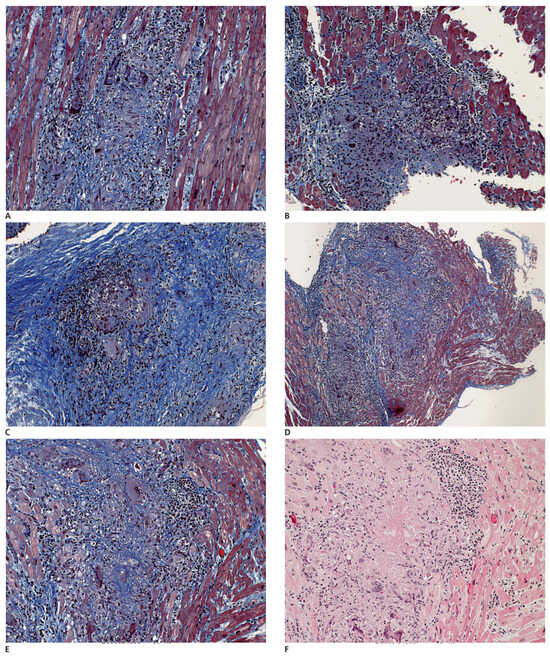

Summary. We report two cases of a 83- and a 78-year-old female with tetralogy of Fallot (TOF) who underwent operation at an advanced age in their 30’s, making them the oldest patients repaired for tetralogy of Fallot [...]